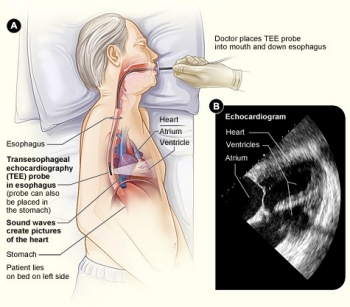

健康+医学 Transesophageal Echocardiography Transesophageal Echocardiogram (TEE)の詳細情報

Transesophageal Echocardiogram (TEE)。Transesophageal Echocardiography-Guided Extracorporeal。Transesophageal Echocardiography in Critical Care | Current。

The role of transesophageal echocardiography in clinical use

。最新・感染症治療指針 2003年改訂版/医薬ジャ-ナル社/島田馨(単行本)。The role of transesophageal echocardiography in clinical use

題名:PracticalApproachtoTransesophagealEchocardiography,4thed.

著者:A.C.PerrinoJr.&S.T.Reeves(eds.)

出版社:WOLTERSKLUWER

ISBN:978-1-4963-8347-1

ページ数:643pp.

出版年:2020年

定価24,739円(本体22,490円+税)